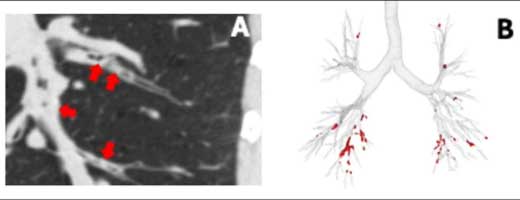

How Does a Comprehensive Approach to Lung Volume Reduction Encompassing Both Surgical and Endobronchial Treatment Translate Into Clinical Benefits?